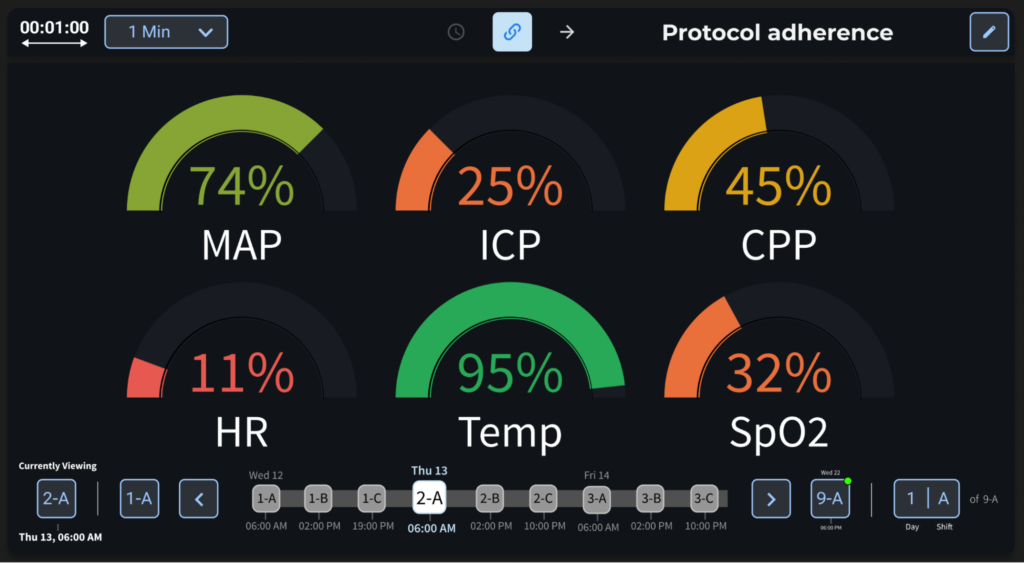

Below is another example of a simple app that displays protocol adherence to basic thresholding guidelines shift-to-shift. This is completely customizable, allowing the user to configure which measurements are shown and what thresholds are used for determining how well the patient was managed. We are also experimenting with the use of the shift selector in the other apps we are developing to aid in the process of nursing handoffs.